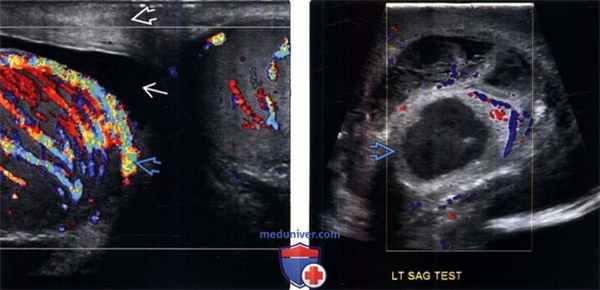

(Слева) Энергетическая допплерография в косой плоскости: заметно увеличенный гипоэхогенный придаток с увеличенным кровотоком. Такие признаки характерны для острого эпидидимита. Обратите внимание на нормальное яичко и гидроцеле.

(Справа) На цветовой допплерографии левого придатка определяется заметно гиперемированный хвост с центрально расположенным гетерогенным гипоэхогенным образованием. Такие признаки характерны для эпидидимита, осложненного абсцессом придатка.

(Слева) На цветовой допплерографии яичек в поперечной плоскости определяется заметно гиперваскулярное правое яичко по сравнению с левым. Данные признаки характерны для правостороннего орхита. В дополнение, отмечаются ассоциированные признаки утолщения стенки мошонки и небольшое гидроцеле.

(Справа) Цветовая допплерография левого яичка у пациента, поступившего с острым эпидидимо-орхитом: гипоэхогенное образование яичка с утолщенными стенками Эти признаки характерны для абсцесса яичка.